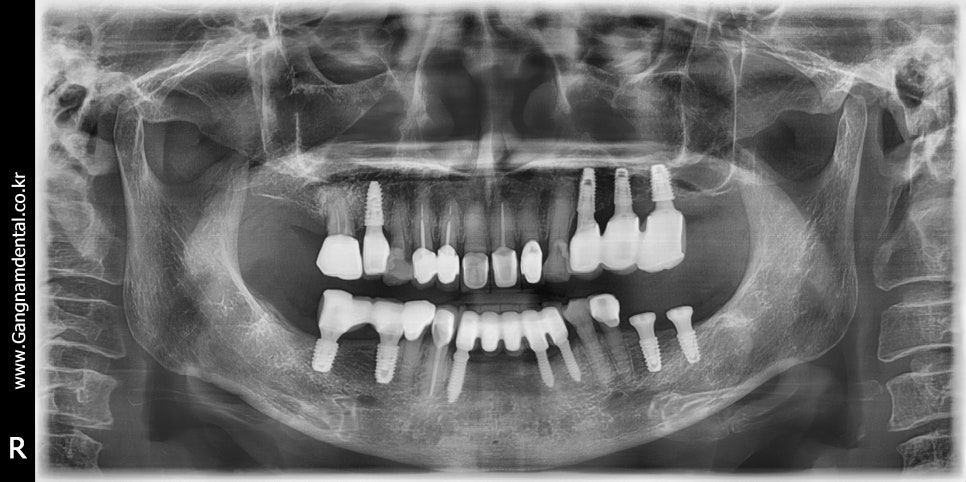

김영삼 원장님 라이브서저리 세미나에서 심은 내 첫 임플란트 케이스 (36i, 37i)

위 사진은 김영삼 원장님께 배운 기본기를 활용해서 심은 내 첫 임플란트 케이스인데, 물론 완벽하다고는 못하겠고 조금 아쉬움이 남기는 해도 처음 심는 임플란트치고 케이스 잘 골라서 잘 심었다고 칭찬도 들었다. 식립하고 정확히 세 달이 지나고는 보철도 올렸다.

아무튼 이 케이스에서 104p에 있는 깊이조절 테크닉을 사용했기 때문에 한 번 올려봤다. 아래 ppt 내용 중에 45도 각도로 토크랜치를 8번, 4번 사용했다는 말이 바로 원장님 책 104p에 적힌 내용을 활용한 것이다.